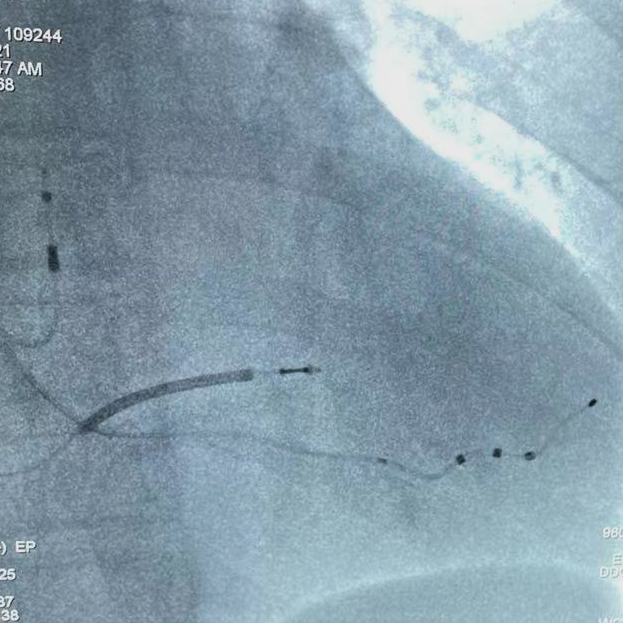

通过术中球囊造影可见,该患者的心脏存在多根可选的靶静脉,沈敏教授分析了每根血管的特点之后,决定选用波士顿科学Acuity X4 Spiral S(型号4674)左室四极导线,首先尝试置入患者的前侧静脉,但由于该静脉相对短且迂曲,左室导线上的四个电极无法完全进入该静脉血管。为了保证最佳的CRT疗效,沈敏教授决定放弃前侧静脉,并尝试植入心后静脉,最终顺利将该左室四极导线推送至静脉远端,固定牢靠,起搏阈值良好,无膈神经刺激出现。该病例充分展示了X4左室四极导线在不同血管中的表现,尤其是Acuity X4 Spiral S左室四极导线上3D立体螺旋在血管近端固定上的优势。

术中造影图像和最终电极位置